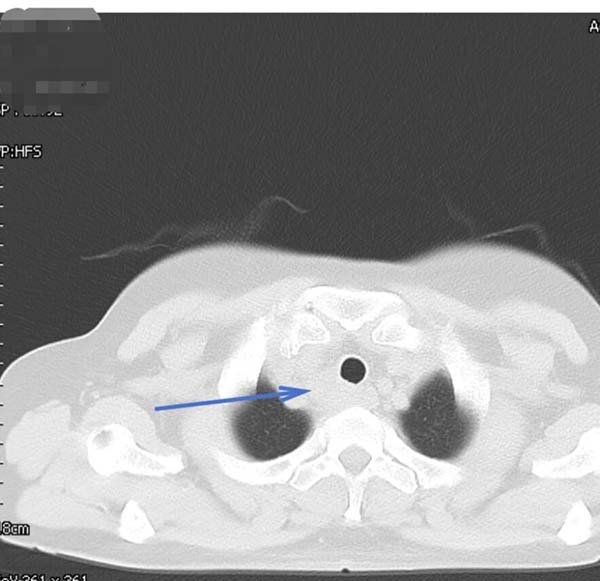

经过胸外科团队的成功采样,医院病理科专家当晚即对穿刺标本进行分析,镜下可见真菌菌丝,形态符合曲霉菌感染,未见恶性肿瘤细胞。“不是癌,是感染!”这个结果让所有人松了一口气。医疗团队随即为患者制定抗真菌治疗方案,经系统治疗后,患者吞咽哽咽感明显缓解,复查影像显示病灶显著缩小。

▲治疗后一个月胸部CT

从影像学高度怀疑恶性肿瘤,到最终明确诊断为曲霉菌感染,这一诊疗过程充分体现了现代精准医疗的价值。通过EBUS-TBNA这一微创技术,患者避免了不必要的创伤性大手术和放化疗。而这场“抽丝剥茧”的背后,是医院放射科、微创中心(第二手术区)、病理科、胸外科等多学科团队紧密协作、高效沟通的结果,彰显了医院在复杂疾病诊疗中的综合实力。